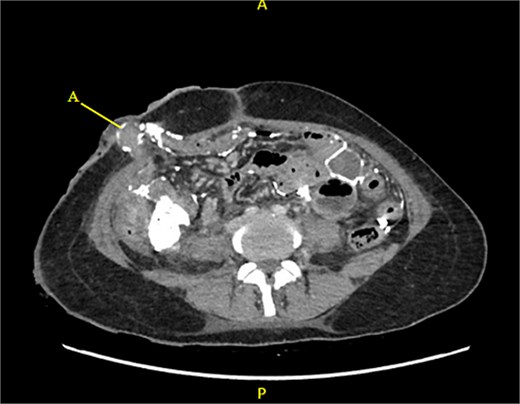

Contrast-enhanced CT of the abdomen and pelvis revealed extensive barium extravasation outlining the peritoneal cavity, accompanied by pneumoperitoneum (Fig. 3). Two barium-outlined, walled-off intra-abdominal collections were identified: one located anterior to the lower pole of the left kidney and the other in the pelvis, anterior to the rectum (Figs 4 and 5). Due to significant barium-related imaging artifacts, the precise site of bowel perforation was not identified. A diagnosis of peritonitis secondary to barium spillage was established, with associated intra-abdominal collections.

CT contrast abdomen and pelvis showing spill of barium outlining the peritoneal cavity. Stoma at the right side of the abdomen (A).